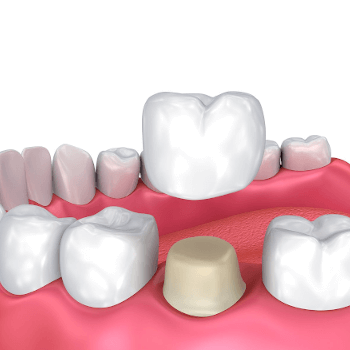

A temporary is a crown or bridge that is placed on the prepared teeth while the final restoration is being made. The temporary serves a very important purpose. It protects the exposed dentin so it is not overly sensitive, prevents food and bacteria from collecting on the prepared teeth, and prevents the tooth from shifting or moving, which can make seating of the final restoration more difficult.

Final Crown or Bridge: